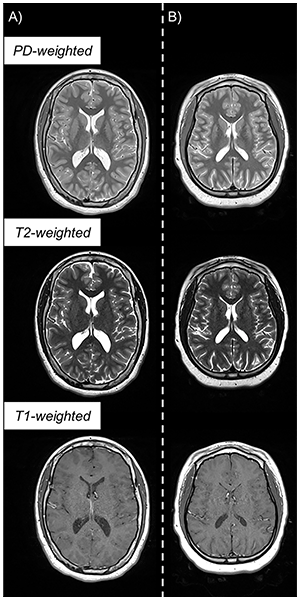

Example triple turbo spin-echo brain MRI scans in (A) neurotypically developing and (B) atypically developing extremely preterm–born adolescents. Proton density (PD)–weighted, T2-weighted, and T1-weighted images are provided. MRI scans in the atypically developing participant demonstrated qualitatively smaller white and gray matter volumes and nearly indistinguishable tissue contrast compared with the neurotypically developing participant.

McNaughton et al, Radiology 2022; 000:1-9 ©RSNA 2022